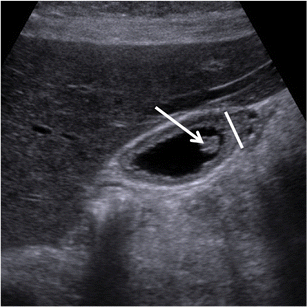

Avascular spaces, representing RAS, must be observed within the thickened gallbladder wall (Fig. 9). RAS appear avascular in every phase of the dynamic study, independently from their content. The identification of avascular spaces within a gallbladder wall thickening is virtually pathognomonic for GA.

Fig. 9

Gallbladder adenomyomatosis: typical contrast-enhanced ultrasound (CEUS) findings. On CEUS, the thickened gallbladder wall shows discrete contrast enhancement, whereas Rokitansky–Aschoff sinuses (arrows) appear as avascular structures during every phase of the exam

Intramural avascular spaces are best appreciated 70100 s after endovenous contrast material administration when the gallbladder wall shows a homogeneous high-degree enhancement.